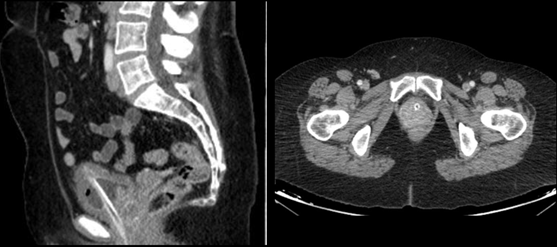

Given this finding, an urodynamic study (UDS) was performed and showed an increased sensibility associated with involuntary detrusor contractions and lower urinary tract obstruction (Figure. 1). Pelvic MRI revealed a solid mass depending on the urethra causing stricture (Figure. 2) and the CT scan identified a heterogeneous 7x6cm mass around the urethra that infiltrated the posterior bladder wall (Figure. 3). Cystoscopy allowed the visualization of membranous tissue with fibrotic aspect on the urethra and a normal bladder without tumors. Biopsies were taken in the same procedure and urine cytology. Results were inconclusive but suggested urethral clear cell carcinoma, therefore it was discussed in a multidisciplinary committee formed by urologists, oncologists, radiologists, nuclear radiologists, and radiotherapists in which radical surgery with curative means was decided.

Figure 3 CT scan. A) Sagittal section shows a 7x6cm paraurethral mass with heterogeneous contrast caption that infiltrates the posterior wall of the bladder. Thickened bladder walls and urinary catheter. B) Transverse section of paraurethral mass with urethral catheterization.